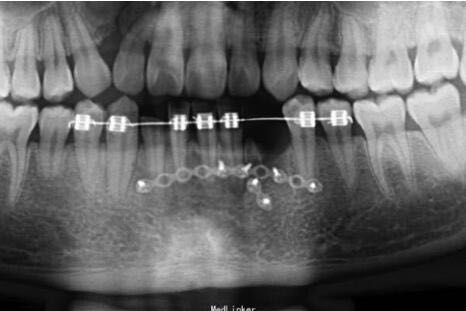

下颌前部可见唇与牙龈的撕裂、肿胀、牙松动,摇动损伤区的牙时,可见邻近数牙及骨折片随之移动,咬合错乱

下颌骨前部牙槽突骨折,下颌骨骨折 处理:托槽固定下颌牙槽突骨折,坚固固定内固定固定下颌骨骨折

术后一个月拆除托槽,CT提示下颌骨骨折愈合中